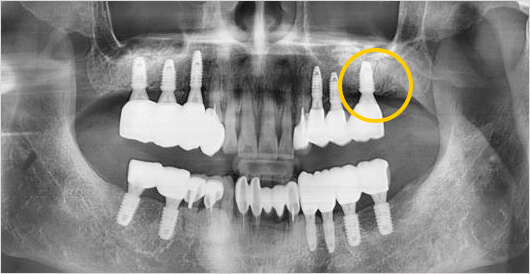

고난이도 임플란트 (상악동 거상술) 수술 전

고난이도 임플란트 (상악동 거상술) 수술 후